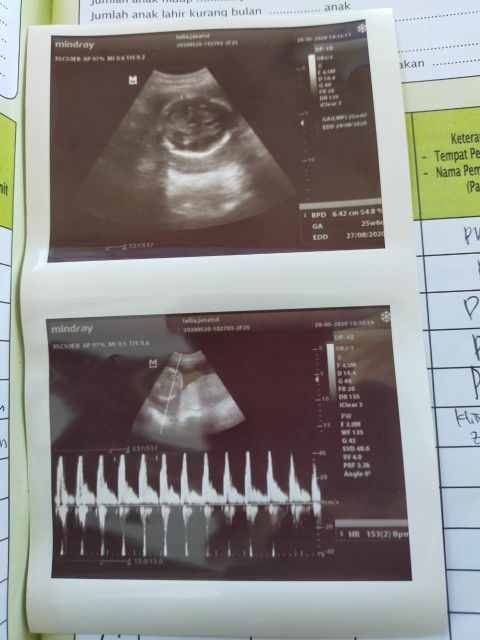

letak plasenta di bawah

Bun dsini ada gk yg waktu hamil letak plasentanya dibawah,,ini aq hbis usg kta dokternya letak plasentanya dibawah seharusnya kan ada diatas/disamping...trus klo mau letaknya berubah gmn ya bun hrus apa ya bun soalnya aq khawatir